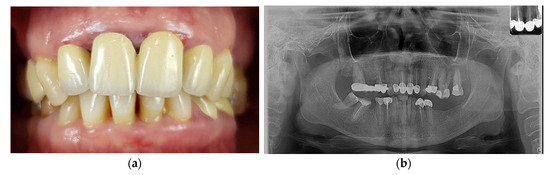

2. Case Report